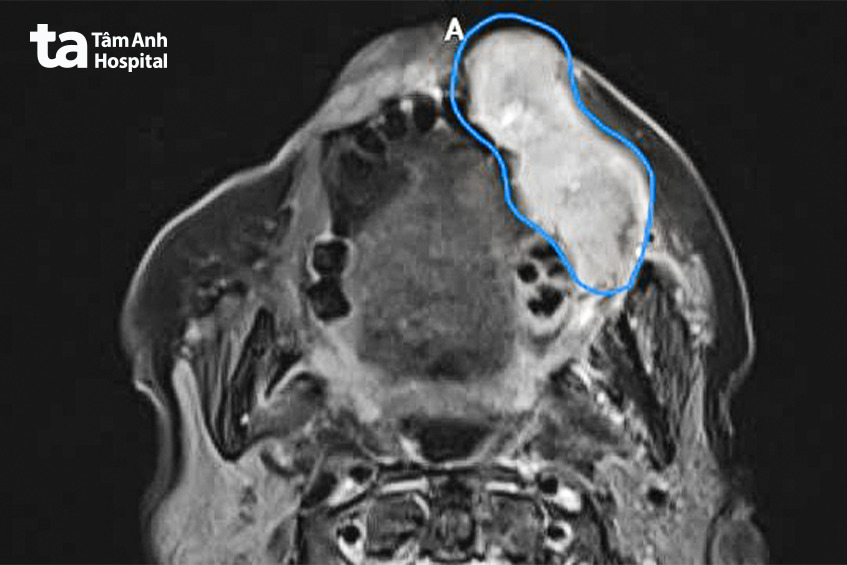

Tại Trung tâm Ung bướu, Bệnh viện Đa khoa Tâm Anh TP.HCM (cơ sở P.Tân Sơn Hòa – Q.Tân Bình cũ), kết quả sinh thiết xác định bà Tình mắc ung thư niêm mạc má giai đoạn 3, khối u lớn, dài 7cm, dày 4cm. Đây là một loại ung thư vùng ổ miệng, thường gặp ở người cao tuổi và có xu hướng tiến triển nhanh. Bà có thói quen nhai trầu rất nhiều và đây là một trong những yếu tố nguy cơ chính gây ung thư ổ miệng tại Việt Nam.

Khối u niêm mạc ác tính kéo dài từ gò má trái xuống cằm, ăn mòn xương, che lấp ổ miệng khiến bà Tình (80 tuổi, Đồng Nai) biến dạng mặt, không ăn uống, nói chuyện được.